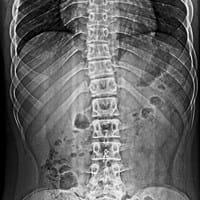

¿Qué deporte se puede realizar para evitar que la escoliosis se acentúe mas?